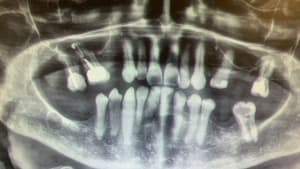

Chirurgie guidée mise en charge immédiate 005.jpg

Chirurgie guidée mise en charge immédiate 004.jpg

Chirurgie guidée mise en charge immédiate 003.jpg